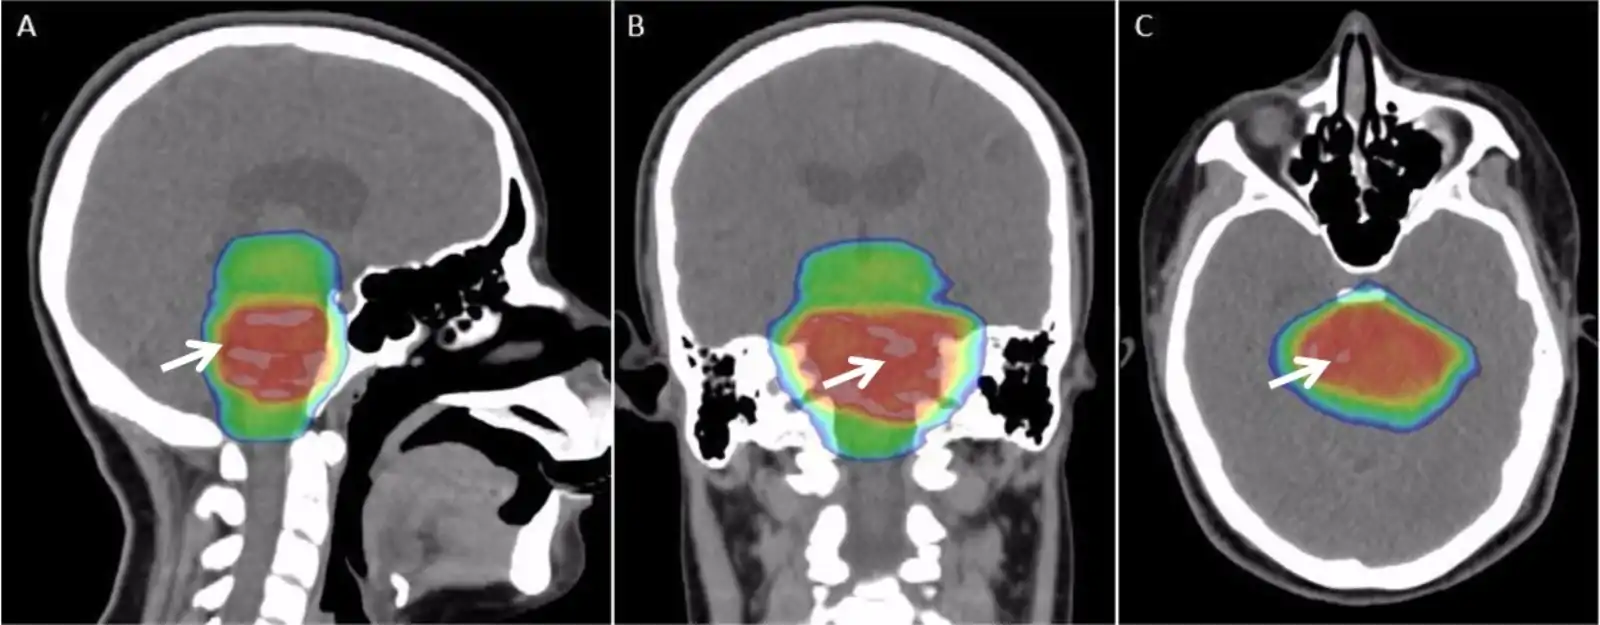

- پرتوشناسی